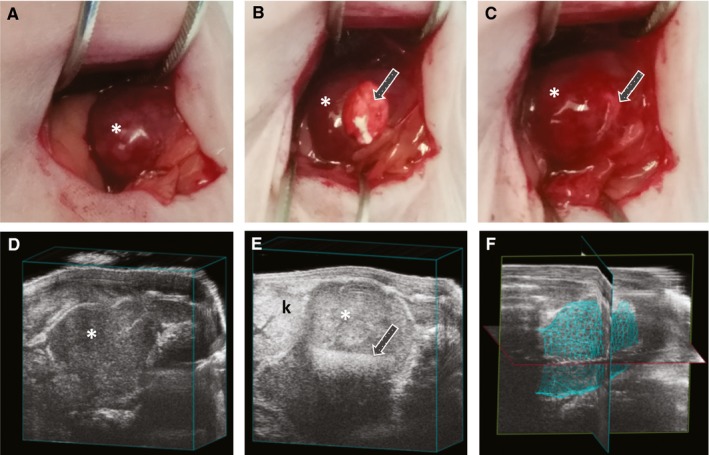

To determine the in vivo efficacy of the dinutuximab release system, xenograft studies were performed using a mouse orthotopic neuroblastoma model using the high‐GD2 expressing KELLY neuroblastoma cells. Once the orthotopic neuroblastoma tumors reached 100 mm3 by ultrasound, mice underwent implantation of silk foam that was dinutuximab‐loaded, human IgG‐loaded (antibody control), or buffer‐loaded (negative control) (Figure 4). There was no difference in initial tumor size between the various groups. Tumors treated with dinutuximab‐loaded silk foam reached 500 mm3 after 4.22 ± 2.05 days, significantly slower than tumors treated with buffer‐loaded silk foam (1.74 ± 1.46 days, P = .02) or IgG‐loaded foam (1.85 ± 1.06 days, P = .009) (Figure 5A). Similarly, tumors treated with dinutuximab‐loaded silk foam reached 600, 700, and 800 mm3 significantly slower than either IgG‐ or buffer‐loaded silk foam treated tumors (Figure 5B‐D). There was no significant difference in the timing to reach 500, 600, 700, or 800 mm3 between tumors treated with buffer‐ or IgG‐loaded silk foam (P = .9, .9, .7, and .6, respectively). Dinutuximab‐loaded silk foam treatment was more effective at decreasing tumor growth compared to IgG‐ or buffer loaded‐foam. Finally, there was no significant difference in animal weights across the treatment groups.

Figure 4.

Implantation of silk foam into orthotopic neuroblastoma and ultrasound imaging. Orthotopic neuroblastoma (A) just prior to implantation of silk foam, (B) with silk foam halfway implanted and (C) completely implanted. Tumor growth/volume was followed with high‐frequency ultrasound (D) before and (E) after treatment with silk foam; (F) representative 3D image of tumor used to obtain volumetric measurements. Asterisk (*) indicates tumor location; arrow (→) denotes position of silk foam within the tumor; k indicates the left kidney